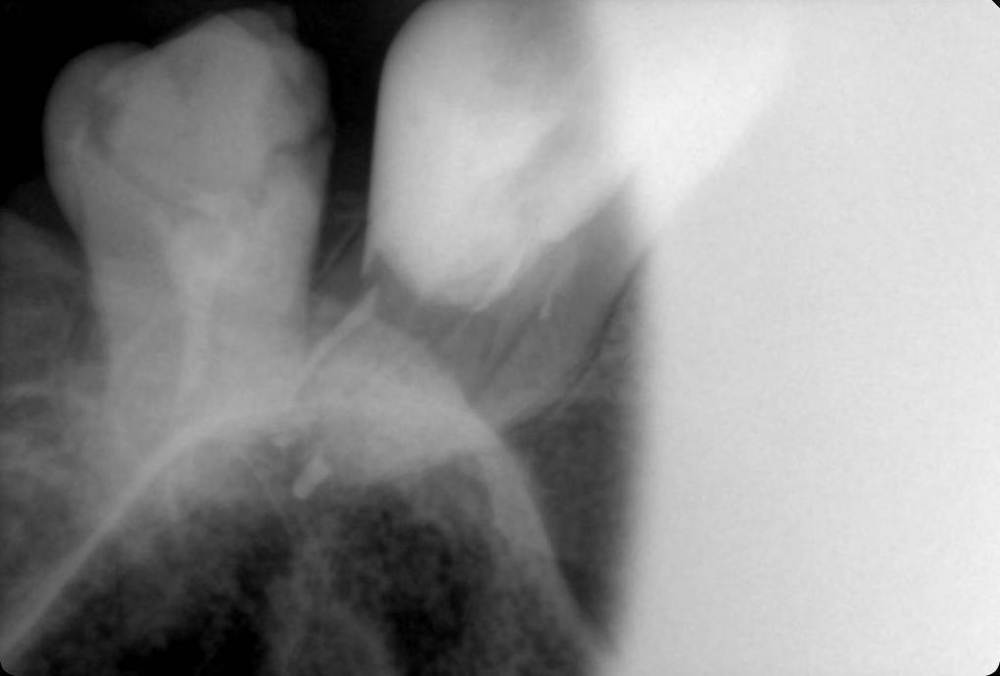

GENRY Опубликовано 6 сентября, 2021 Поделиться Опубликовано 6 сентября, 2021 Здравствуйте! Как лучше восстановить ( пусть частично) 28 зуб? Удаление не желательно т.к. с имплантацией связываться не хочу (синус лифтинг.. возраст 75 лет...) ,а опор для ортопедических конструкций нет. Кроме того боюсь, что в процессе удаления будет разрушена пломба 27 _го. Оптимизма добавляет история 27 го На орто 2012г показан 27 до его восстановления и до вмешательства в 28 зуб с добавлением в него пломбы в 2012г . Канал 28_го (небный ?) был уже запломбирован кем то раньше, скорее всего резорцин-формалиновой пастой) Доктор в 27 - м обнаружил на снимках 3 канала, наполовину прошел небный и полностью прошел дистально- щечный канал с наполнением их горячей гуттаперчей . Поскольку устье 3_го канала обнаружено не было, восстановил 27 зуб 2_мя стекловолоконными штифтами с использованием Build-It . Дистальную стенку сделал, кажется на основе пасты СПЕКТРУМ . К дальнейшей судьбе 27_го доктор отнесся скептически ( не более 2_х лет!), но похоже сработал надежно, пошел уже 10_й год, а 27 все стоит. Но 10 мес. назад выпала пломба 28 _го и он принял вид показанный на снимке. Не беспокоит. Хотелось бы повторить историю с 27_м, т.е. восстановить 28 по типу 27_го .... думаю мне хватит 5_7 лет... Регулировать нагрузки на этой стороне челюсти я научился. Сделал КТ сегмента 27_28 (В Пикассо, Vatech, просмотрщик EZ3D2009 plus ) но не смог найти ( сейчас живу в Феодосии ) терапевта работающего с этой программой. Кто то вообще не использует никакие КТ (но при этом берется за восстановление штифтом без перелечивания каналов) , кто то готов к перелечиванию, но полагается только на свои мануальные навыки, игнорируя КТ или формально глянув на пару проекций. На последней консультации добился 4-х снимков из КТ, но в общем то случайных и скорее всего не показательных.. Выкладываю скриншоты... Понял, что надо выходить за пределы городка и расширять собственное (к сожалению) понимание возможных вариантов лечения и их последствий. Вопросы по 28: 1. Если хотя бы один канал запломбирован (видимый на снимке) то это автоматически означает вскрытие камеры , а значит вскрытие и убитость содержимого (нервов, сосудов) всех остальных каналов , поскольку их устья на дне камеры? (Да, Нет, Другое) 2. Если Да, то нормально ли было пломбировать 28, не найдя и не залечив (с пломбировкой) другие каналы одновременно с небным (я имею ввиду сейчас самую раннюю пломбировку, до представленного орто) 3. Поскольку пломбировки всех каналов (сколько их ?) точно не было, то за эти 10-15 (?) лет (уже сейчас зуб стоит открытым почти год (ковид, консультации..)) должен развится пульпит, периодонтит... ? Или не обязательно? Ничего не болело, никаких выделений не было 4. Есть ли признаки какой либо хроники, воспалений в тканях на снимках? 5. Если ткани зуба и около него в порядке, то может не обязательно перелечивать все каналы, чтобы не ослаблять зуб? А только те, в которые будут вставлены штифты? Вкладка, похоже исключается т.к. феррул не замкнут на стыке с 27 зубом. 6. Есть ли какие либо оценки минимального количества требуемых штифтов ? 7 . Поскольку за 4 консультации я так и не получил ответов и снимков срезов (по КТ )показывающих количество и топологию корней и каналов, то придется добывать эту информацию самому. Буду благодарен за ссылки на материалы показывающих как это делается т.е. в каких из 3 проекций, при каком положении осей и.т.п. Я нашел только хороший ролик Ервандяна А.Г., но мне недостаточно, не хватает знания топологии зубов. Спасибо за внимание. Ссылка на комментарий

GENRY Опубликовано 8 сентября, 2021 Автор Поделиться Опубликовано 8 сентября, 2021 12 часов назад, dentikl сказал: покажите плз фото нижних и верхних передних зубов.Можно телефоном.Верхние-чтобы увидеть режущий край (если он сохранен) Представленная раньше орто сделана в 2012г. Произошли изменения: 11,21,22 - живые с коронками; 12 - коронка на вкладке; 24 - был треснут, эндопролечен (фото прилагается), восстановлен; 13,23 - живые, но сильно стерты, особенно у десны . Займусь ими после разборки с 28 (и 18). они стоят открытые, На 17 одета металлическая коронка. 18 лишился пломбы 2 мес. назад. На след. неделе еду на его лечение. Снимок 17,18 перед лечением в 2013 _ прилагаю Ссылка на комментарий